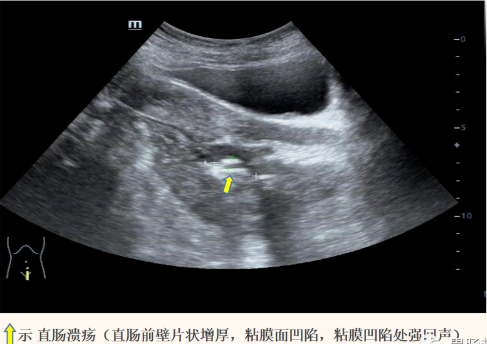

• 直肠肠壁可见多发低回声结节向腔内隆起,较大着位于直肠后壁,大小约5.2x3.3x2.0cm(长x宽x厚),前壁另可见片状不规则增厚,较厚处约1.1cm,累及长度约4.0cm(环绕肠壁约1/2周),肠粘膜面可见一较大凹陷,长约2.2cm,深约0.7cm,粘膜凹陷处可见强回声附着。

直肠后壁及右侧壁低回声结节明显减小,部分小结节已不能清晰显示,仅可见两个低回声结节,大小分别约2.1x1.1cm,1.5x1.1cm,直肠壁稍厚,厚约0.6cm,粘膜面直肠溃疡变浅,直肠无明显狭窄。患者自述大便顺畅无不适。